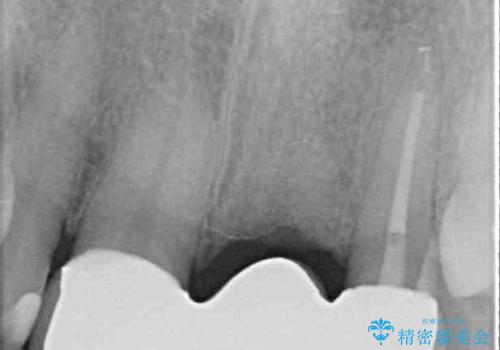

神経の抜かれている土台の歯は根管治療を行った上で、オールセラミックブリッジにより補綴することとしました。

術前の状態より、欠損部位には歯肉移植術が必要と思われましたが、仮歯で調整したところ自然な歯列となったため、外科処置は行わずに自然な口元に仕上がりました。